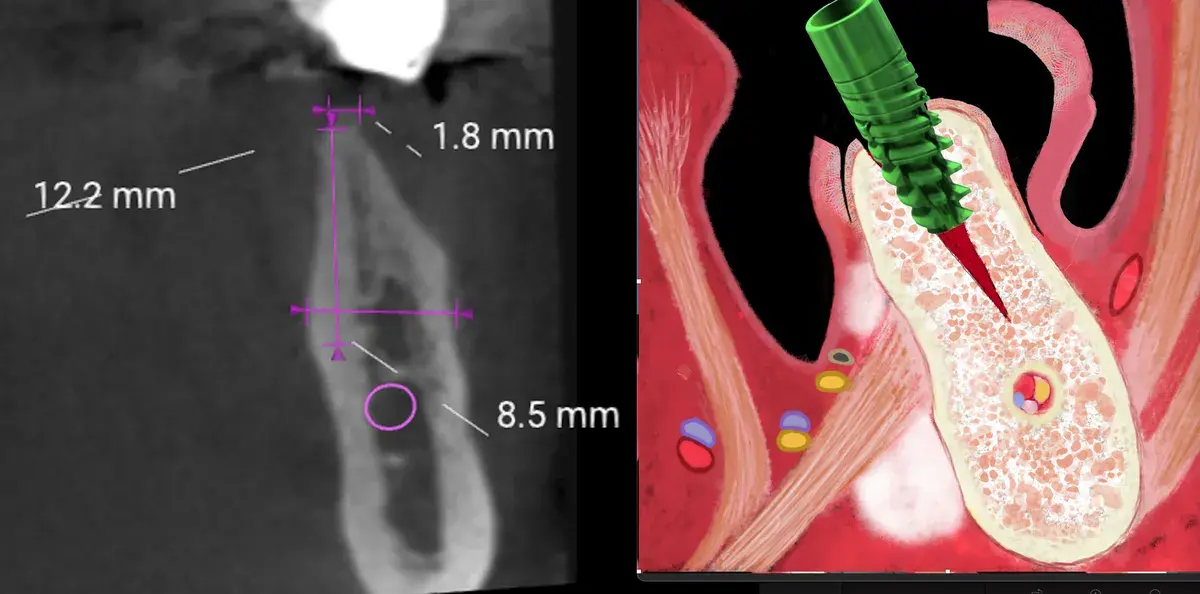

Bone-level, tissue-level, connessione conica: la profondità corretta cambia con il tipo di connessione. Perché sbagliarla causa riassorbimento osseo.

Scopri i principi fondamentali per il posizionamento corretto degli impianti e l'uso di connessioni coniche e MUA, per prevenire la peri-implantite e l'...